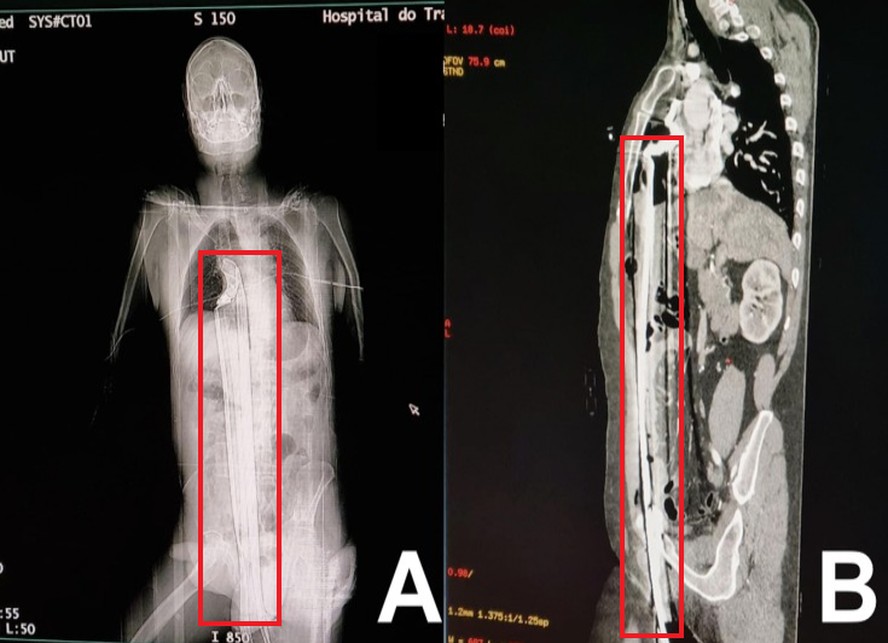

A história impressionante de um homem brasileiro virou estudo de caso em um jornal médico internacional: um curitibano, de 57 anos, escapou da morte após ser empalado por uma barra de ferro no períneo após cair de uma altura de cinco metros em um acidente. O homem não foi identificado para manter sua privacidade, mas já é considerado um milagre devido às extensões dos danos.

O atendimento ocorreu no Hospital do Trabalhador, em Curitiba, e chamou atenção pela área delicada onde o objeto perfurou o corpo do homem. A barra de ferro atravessou seu fígado e atingiu o topo do diafragma, errando por pouco o coração.

Imagens da barra de ferro atravessando o corpo do homemImagens da barra de ferro atravessando o corpo do homem — Foto: Reprodução

Na publicação, os médicos revelaram que o homem precisou passar por uma complexa cirurgia para escapar, não desenvolveu problemas a longo prazo e teve alta em apenas três dias. Chegando ao hospital, o homem foi levado às pressas para uma cirurgia de emergência de esternotomia – onde o esterno é cortado e dividido para alcançar a barra de ferro.